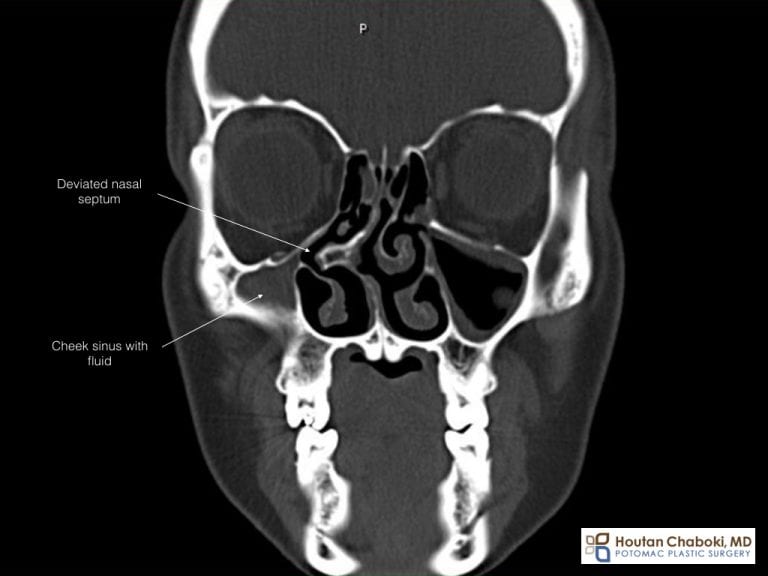

From www.potomacplasticsurgery.com

Rhinoplasty and Septoplasty for Bone Spur What Is A Spur In Your Nose In this article, we’ll explore what a nasal septal spur is, how it develops, and. The two cavities of your nose. A deviated septum can be. Nasal bone spurs are when these bony. It is a short bend either happening in the. Bone spurs of the nose are primarily caused by repetitive stress to the bones in the nose. Excess. What Is A Spur In Your Nose.